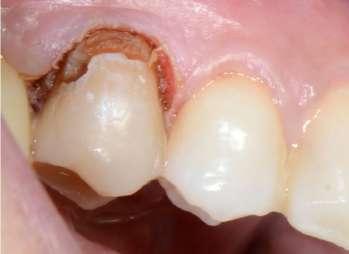

Paziente femmina, 38 anni che presenta carie cervicale dell’elemento 1.5. Gengivectomia con manipolo angolato, tip in zaffiro con diametro di 400 μm, lunghezza 12 mm, 2.4 W, 20 Hz, 120 mJ E per impulso, potenza di picco 750 W, densità di potenza media 659 W/cm2, densità di potenza di picco 205,860 W/cm2, energia totale 432 J, larghezza impulso 160 μs, distanza tip-tessuto 1 mm, 50% acqua, 50% aria, tempo totale di trafamento 180 sec. Impostazioni dello smalto: manipolo angolato, tip in zaffiro diametro 800 μm, lunghezza 12 mm, totale energia 810 J, ampiezza dell’impulso 160 μs, distanza tip-tessuto 1 mm, 100% acqua, 70% aria, tempo di trafamento totale 180 sec.

Impostazioni dentina e smear layer: tip in zaffiro con diametro 800 μm, lunghezza 12 mm, 3.3 W, 20 Hz, 165 mJ, potenza di picco 1031 W, densità di potenza media 360 W/cm2, densità di potenza di picco 112,346 W/cm2, energia totale 594 J, ampiezza dell’impulso 160 μs, distanza tip-tessuto 1 mm, 100% acqua (18 ml/min), 70% aria, tempo di trafamento totale 120 sec.

Fig. 1 – Cavità su 1.5 Fig. 2 – Particolare della cavità del dente 1.5 Fig. 3 – Preparazione Laser Er:YAG Pluser con lunghezza d’onda di 2940 nm di LAMBDA DoctorSmile, Italia. Fig. 4 – Particolare della cavità dopo gengivectomia Fig. 5 – Particolare della cavità completata dopo la preparazione della dentina Fig. 6 – Restauro finale in composito (Asteria Tokuyama, Japan)